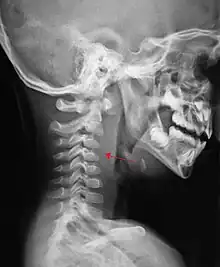

| A lateral cervical spine x-ray demonstrating prevertebral soft tissue swelling (marked by the arrow) as seen in a person with a retropharyngeal abscess | |

X-ray of the neck often (80% of the time) shows swelling of the retropharyngeal space in affected individuals. If the retropharyngeal space is more than half of the size of the C2 vertebra, it may indicate retropharyngeal abscess.[5]